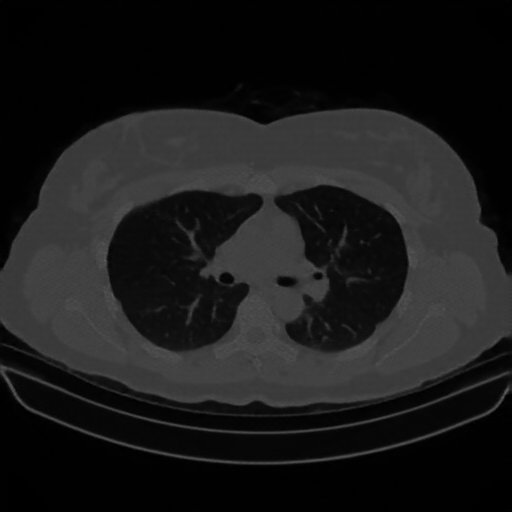

Original VENOUS CT scan

Full window (WL 1023.5, WW 4095 β†’ Low βˆ’1024, High +3071)

Lung window (WL -600, WW 1500 β†’ Low βˆ’1350, High +150)

Mediastinum window (WL 40, WW 400 β†’ Low βˆ’160, High +240)